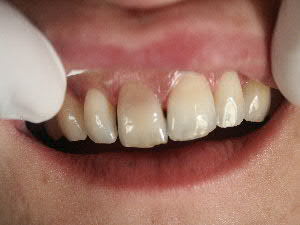

facettes 11 et 21...

blanchiment externe au fauteuil(bluecool ou autre) ou ambulatoire a concentration elevee

cela te permet de repousser encore l'etape facettes plus mutilante

-pour les habitués des facettes : une facette permettra t'elle de faire disparaitre totalement la coloration et de rendre les caractérisations marquées de la dent adjacente,faut il tailler plus profondement que pour une facette classique,quelle type de céramique utiliser

Si tu utilises de la céramique Dicor tu peux masquer les colorations, esthétiquement ça vaut pas l'empress.